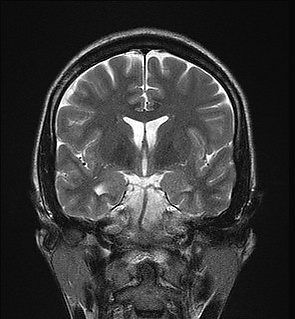

Склероз гиппокампа

Склероз гиппокампа — гибель нейронов и глиоз нервной ткани гиппокампа. Чаще всего склероз гиппокампа отмечается при височной эпилепсии — по некоторым оценкам, у 65 % пациентов. До 16 % случаев деменции также могут сопровождаться склерозом гиппокампа.(Dickson et al., 2004; Leverenz et al., 2002; White et al., 2002)